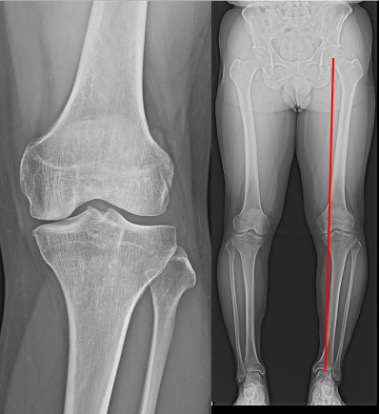

高位脛骨骨切り術(high tibial osteotomy: HTO)

初期の変形性膝関節症や大腿骨顆骨壊死などに適応があります。

O脚変形のために内側に偏った荷重線を、自分の骨を骨折させ角度を変えることにより、比較的きれいな軟骨の存在する外側に荷重線を移動させる手術です。荷重線が移動することによって膝の痛みが緩和されます。

膝関節そのものは温存されるため、人工膝関節置換術では困難な正座やスポーツ活動へ復帰された患者さんが多くいらっしゃいます。